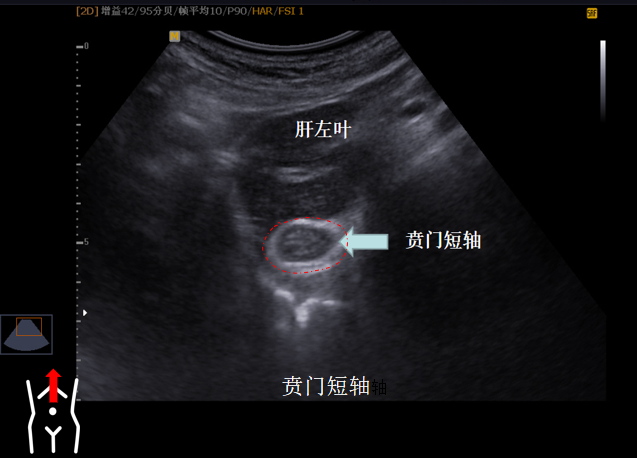

第一组贲门切面

受检者平卧位我们将探头置放剑突区以肝左叶及腹主动脉作为寻找贲门的界面原位旋转探头找到食道下段及与贲门连接处轻摆探头将贲门喇叭口清晰显示再将探头向左上翘此时胃底部也可以显示所以第一组切面我们称之为主看贲门附看胃底。